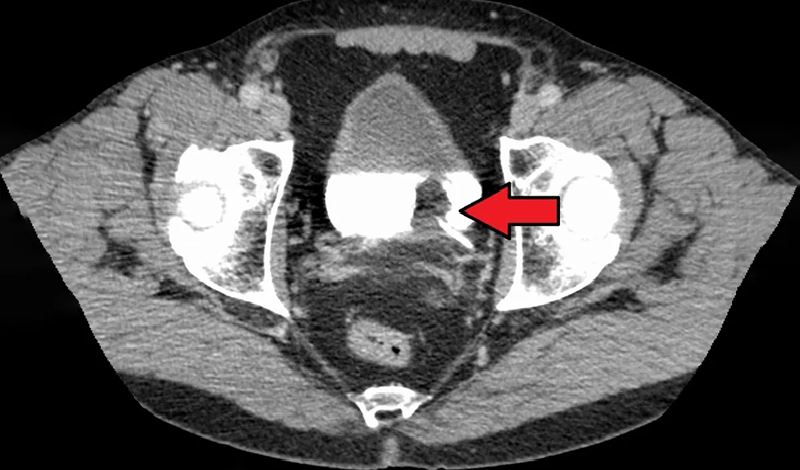

पेशाब की जांच, यूरिन साइटोलॉजी, सिस्टोस्कोपी, सीटी स्कैन और बायोप्सी जैसे मेडिकल टेस्ट की पहचान की जाती है। जिन लोगों को पेशाब के दौरान खून आता है, उन्हें मूत्राशय कैंसर का पता लगाने के लिए ऊपर बताए गए मेडिकल टेस्ट कराने की सलाह दी जाती है।क्या मूत्राशय कैंसर का इलाज संभव है?